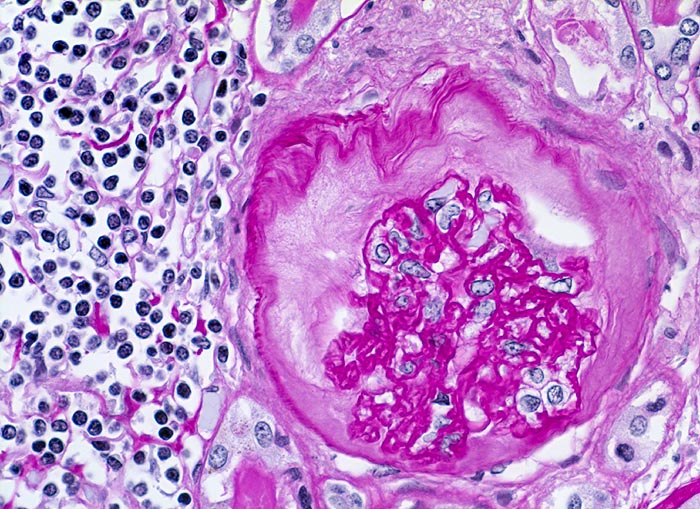

Histologisch finden sich neben völlig unverändertem Parenchym herdförmige Infiltrate aus Lymphozyten, Plasmazellen, Histiozyten und bei akutem Schub zusätzlich neutrophile Granulozyten. Das destruierte Gewebe wird durch Granulationsgewebe im Intersititum organisiert. Gruppen erhaltener Tubuli mit vergrössertem Durchmesser und abgeflachtem Epithel gefüllt mit Harnmukoid (=Tamm-Horsfall Protein und/oder IgA) bilden Pseudostrumaherde (> 1793). Diese sind ein wichtiger Hinweis aber kein Beweis für chronische Pyelonephritis. Bei Kindern finden sich oft zusätzlich Lymphfollikel. Glomeruli kollabieren und zeigen eine konzentrische periglomeruläre Fibrose. Oft findet sich eine Arteriolosklerose und eine adaptative Intimafibrose grösserer Arterien. Obligat findet sich eine schwere chronische Pyelitis sowie eine Fibrose von Nierenbecken und Nierenmark.

Bei fortgeschrittener bilateraler Nierenschädigung kommt es zum Auftreten einer Überlastungsglomerulopathie, die meist unter dem Bild einer segmentalen fokalen Glomerulosklerose in Erscheinung tritt.

• Prominente dickwandige Arterien mit adaptativer Intimafibrose.

• Glomerula mit kollabierten Kapillarschlingen.